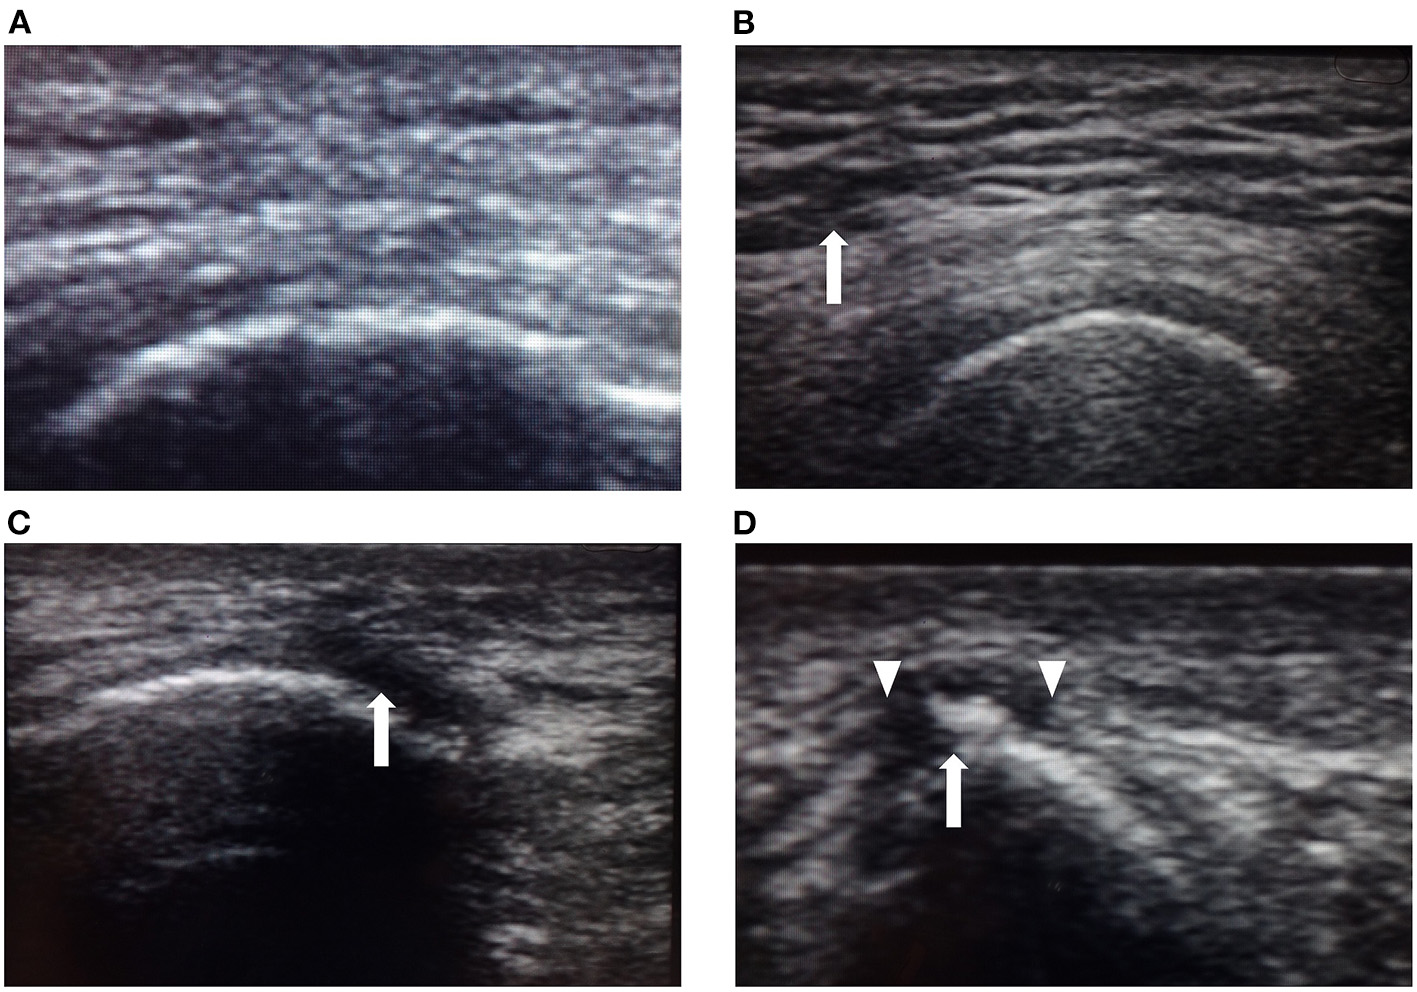

The PI examination used the testing protocol previously described by Kanno et al. (11). Each patient was examined in the prone position as follows: First, one examiner carefully inspected the skin of the right and left ischial regions for the presence of redness, areas of localized purple or chestnut coloring, swelling, or epidermal freshness, excluding old scars or pigmentation due to old wounds. Second, the examiner palpated the same areas to assess localized heat or floating sensation. Third, the same areas were imaged using a high-frequency linear ultrasound array. A single examiner scanned three different aspects to detect both hypo- and hyperechoic lesions in B-mode images from the skin to the bone. The areas examined were classified as normal or abnormal by ultrasound by another physician who was not informed of the diagnosis based on inspection and palpation. Typical ultrasound images of the lesions are shown in Figure 2. Normal lesion areas showed a homogeneous pattern of ultrasound reflections from the epidermis to the bone, with a clearly defined muscle layer. Contrastingly, low-echoic lesions were heterogeneous, with either little or no echogenic signal, which we defined as hypoechoic lesions. Aoi et al. (8) reported four abnormal signs found in deep tissue injury: unclear layered structure, hypoechoic lesion, discontinuous fascia, and heterogeneous hypoechoic area. In our examination, unclear layered structures were often found even in areas where hypoechoic lesions were not present, and judged separately from low-echoic lesions.

Figure 2

Typical ultrasound images. (A) Ultrasound image of normal skin showing a homogeneous pattern of ultrasonic reflections from the epidermis to the right ischial bone (arrow), with a clear layer of muscle. (B) Unclear layered structure with a coarse echo texture (arrow) is most frequently seen even in areas where hypoechoic lesions are not present and judged separately from low-echoic lesions. (C) Low-echoic lesion near the right ischial region in Case 2. The image shows a hypoechoic area near the bone (arrow). This hypoechoic area did not disappear when compressed. (D) Low-echoic lesion near the right ischial region in Case 7. Heterogeneous hypoechoic areas contained high-echoic areas (arrow). The image shows an unclear layered structure and discontinuous fascia. Discontinuous fascia shows a broken or discontinuous line with heterogeneous echo signals (triangle).